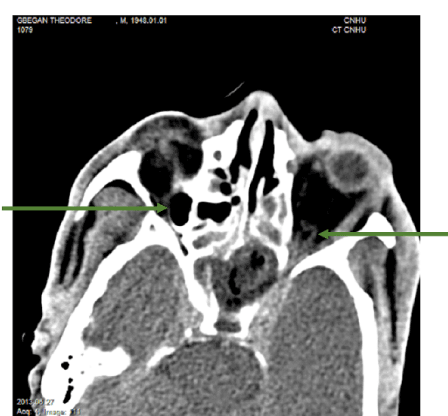

Cerebral orbito computed tomography showed a bilateral hypodense orbital image with its raised wall, hyperdense translating a collection (Figure 2) and a cerebral parietal right hypodense under dural limited by a raised wall, hyperdense (Figure 3).

Figure 2. CT axial section showing:

• a right or left intra orbital abscess in the form of a hypodense image with its raised wall, hyperdense;

• a conglomeration of the ethmoidal cells and an abscess of the left sphenoidal sinus;

• involvement of the cavernous sinuses.